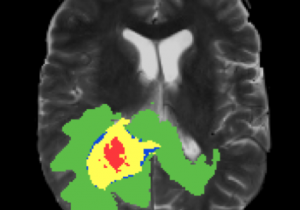

http://Deep%20learning%20for%20brain%20tumor%20segmentation

Jul 4 2021

Research Paper Explores Deep Learning and Brain Tumor Segmentation